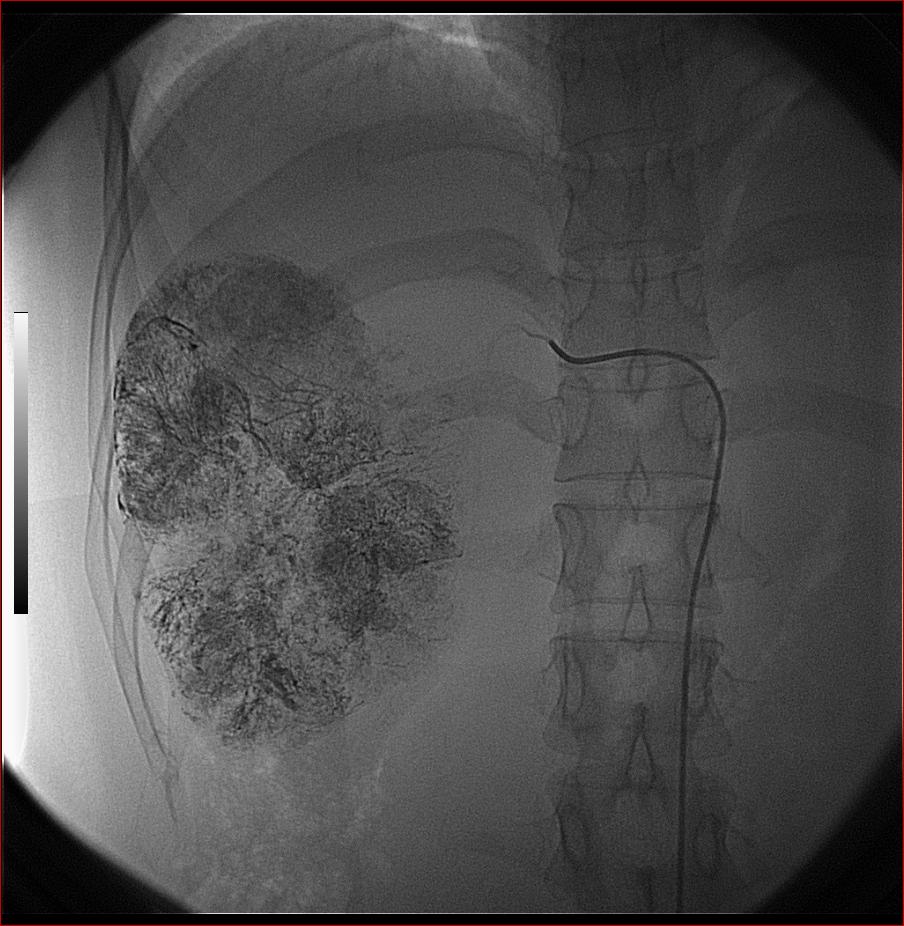

第二次(50天后)

栓塞的非常理想。

好牛的,右肝动脉发自肠系膜上动脉,不用微导管分次进行末梢栓塞,肿瘤染色完整。再次学习了。